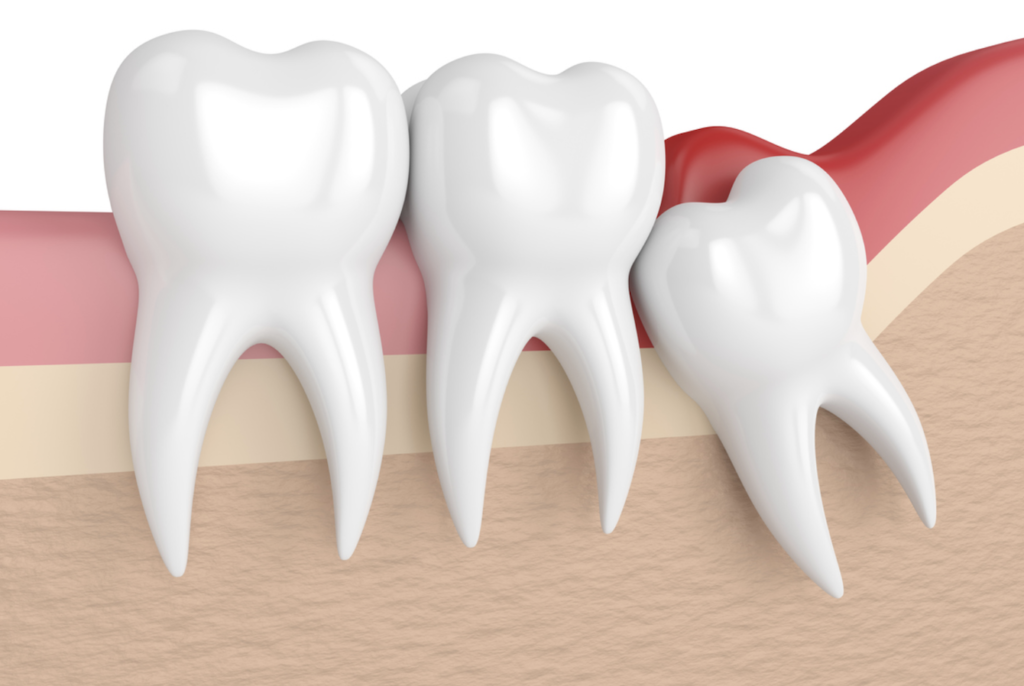

據統計,約75%人有齊4隻智慧齒,約25%人缺少至少一隻智慧齒。當牙弓沒有足夠的地方容納智慧齒,或者智慧齒的生長位置或角度不對,就會令智慧齒不能完全長出,出現阻生智慧齒問題。症狀包括但不限於痛楚、牙肉膿腫、口腔出現異味、面部受影響位置腫脹、張口困難等。

圖一:覆蓋在牙冠上的牙肉容易引起發炎